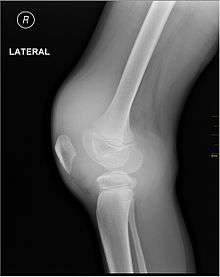

X-ray of Hemarthrosis